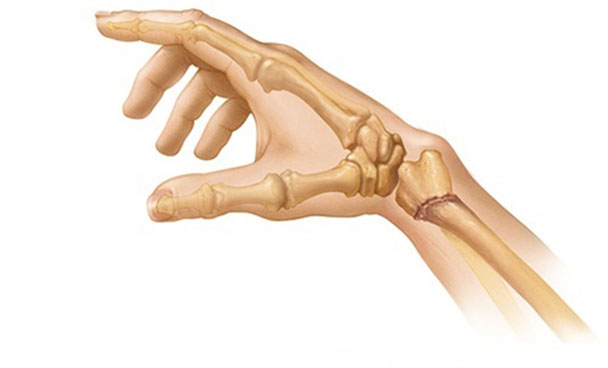

- Смита – отклонение кисти в наружном направлении, при этом происходит одновременное смещение костей (отломок лучевой кости направлен к ладони).

- Коллеса – разгибательная травма приводит к деформации плечевого сустава, напоминающая штыкообразную форму. Травма сопровождается повреждением шиловидного отростка, а у пожилых и людей с повышенной хрупкостью костей происходит дробление в месте перелома.